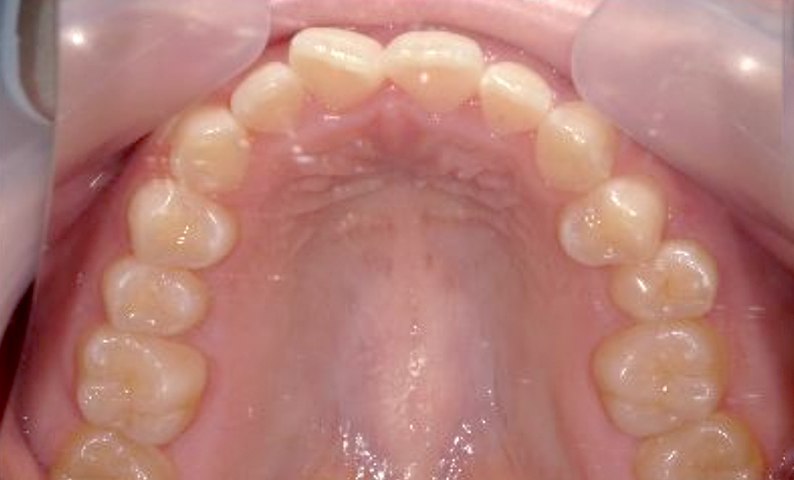

症例_002 前歯「捻転歯」症例

治療期間:7ヶ月金額:27万円+税20代女性少しのねじれ上の前歯だけ

| Before | After |